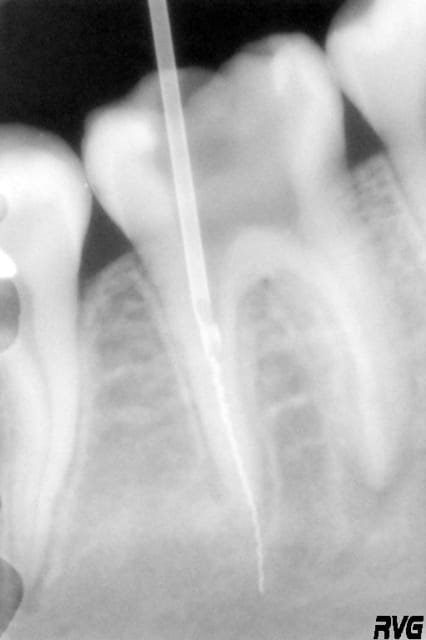

Je peux voir l'instrument à l'oeil nu, j'arrive a mettre l'IRS dessus, mais si je tire, ou si je tente un mouvement de dévissage, l'IRS ressort et l'instrument reste en place pour le moment.

Pareil en passant des racleurs à coté du rispi quasiment jusqu'à l'apex et en tentant un mouvement de remontée : le rispi n'a pas encore bougé.

Je revois la patiente mercredi à 20h ; je me demandais si vous auriez des conseils pour arriver à l'enlever (combien de millimetres d'instrument pris dans l'IRS ; mouvement vertical ou de dévissage ? Utilisation de racleurs pour le remonter...

4eme : rispi en place (j'arrive a le mettre un 1/2 mm plus sur le rispi quand je le lache pas pour prendre une radio)